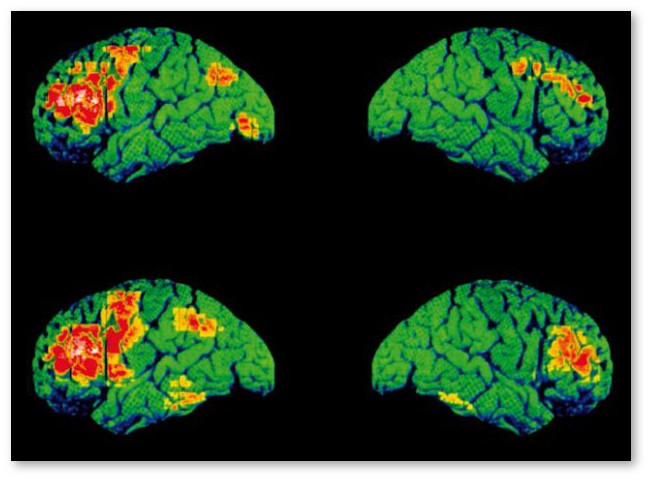

Исследование группы ученых из Университета Манчестера проливает новый свет на то, как употребление марихуаны влияет на шизофрению.

Хотя курение конопли не оказывало прямого влияния на симптомы шизофрении или ее прогноз, настоящее исследование установило, что повышение потребляемых доз марихуаны было умеренно связано с усугублением тревоги и депрессии.

Кажущиеся противоречия говорят скорее о том, что "воздействие конопли на пациентов с психозом очень сложное и неоднозначное", по словам самих ученых. Есть также свидетельства в пользу того, что некоторые вещества марихуаны могут помочь при психических заболеваниях.